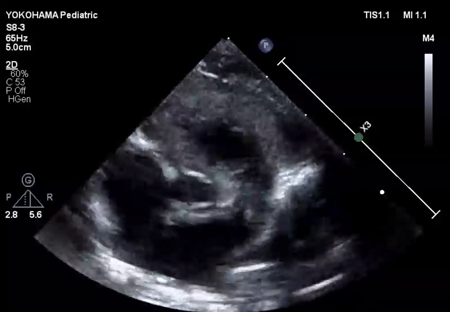

Fig. 1 Echocardiographic findings

(A) Echocardiography at the time of admission (subcostal view) showed only a small slit-like blood flow across the foramen ovale. (B) Echocardiography on admission (four-chamber view) showed a dilated left atrium with an end-systolic volume of 4.0 mL. The left ventricular end-diastolic diameter was normal (15.9 mm). The left ventricular contraction was mildly reduced, with an ejection fraction of 40%. (C) Echocardiography on admission (short axis view) showed a highly echogenic and non-mobile mass (white *) of 10 mm ×5 mm in the left atrial appendage. (D) Echocardiography on day 9 showed improvement in left ventricular contractility. Atrial size had become normal, with a left atrial end-systolic volume of 2.1 mL. LA, left atrium; RA, right atrium.

LV ejection fraction was down to 40% with moderate mitral regurgitation, whereas RV contractility was preserved. The biventricular volumes seemed well-balanced, and the LV end-diastolic diameter (15.9 mm) was within the normal range. Systolic RV pressure was estimated as 70 mmHg by regurgitation flow across the tricuspid valve (velocity 4.1 m/s), indicating persistent pulmonary hypertension. The ductus arteriosus had already closed. The foramen ovale (FO) was patent with very little blood flow through (Fig. 1A). The left atrium (LA) was dilated and non-contractile (Fig. 1B, Supplementary Video S1). Echocardiography showed a highly echogenic mass measuring 10×5 mm in the LA appendage, which was not mobile. The mass was suspected to be a thrombus (Fig. 1C, Supplementary Video S2). Blood tests indicated a high B-type natriuretic peptide (BNP) level (1,102.8 pg/mL) and a mildly elevated D-dimer level (2.27 µg/mL). There was no decrease in platelet count (279×103 /µL) or increase in clotting time (prothrombin time/international normalized ratio: 1.05, activated partial thromboplastin clotting time [APTT]: 29.9 s). The levels of fibrinogen (326 mg/dL), antithrombin-III (65%), protein C (35%), and protein S (68%) were within normal limits for neonates. There was no maternal history of systemic lupus erythematosus or antiphospholipid antibody syndrome, which could have affected neonatal formation of intracardiac thrombi.

We administered diuretics as well as continuous infusion of olprinone and unfractionated heparin. Continuous infusion of heparin was started at 10 U/kg/hr and gradually increased to 20 U/kg/hr, but the APTT was only slightly prolonged to 36.0 seconds on day 9. Daily echocardiography showed gradual improvement in LV function. Olprinone and diuretics were discontinued by day 9, because the LV ejection fraction improved to 65% and the LA size normalized (Fig. 1D, Supplementary Video S3). Marked mobility of the mass appeared in parallel with the restoration of LA contractility on day 10 (Supplementary Video S4). We performed a surgical thrombectomy on cardiopulmonary bypass so as to avoid systemic embolism. A white structure adhering to the LA appendage was excised (Fig. 2A), and pathological diagnosis was a calcified thrombus (Fig. 2B). The postoperative course was uneventful. Low-dose aspirin was started on the 3rd postoperative day. The patient was followed up on an outpatient basis, and aspirin was discontinued at 4 months postoperatively. At the time of this publication, the patient is 2 years old, and she has experienced no recurrent clots or embolic episode thus far.